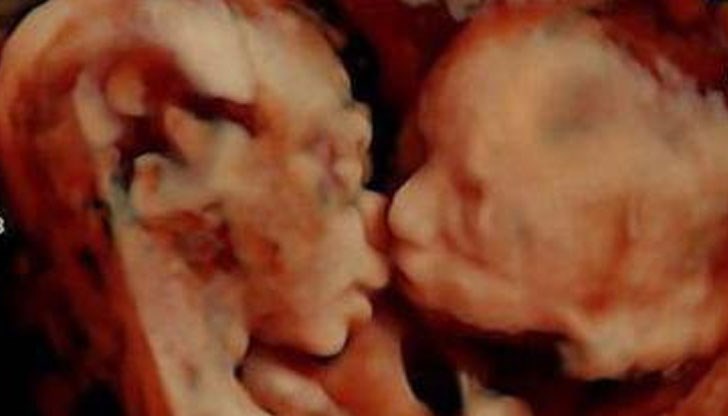

Невероятен момент беше заснет от 3D ултразвук с корема на бременна жена.

В утробата и двете и близначета се целуват, сподели Канал 3.

Забележителната фотография е направена в 25-тата седмица от бременността на Кариса Гил. Тя и съпругът й Ранди се чувстват благословени.